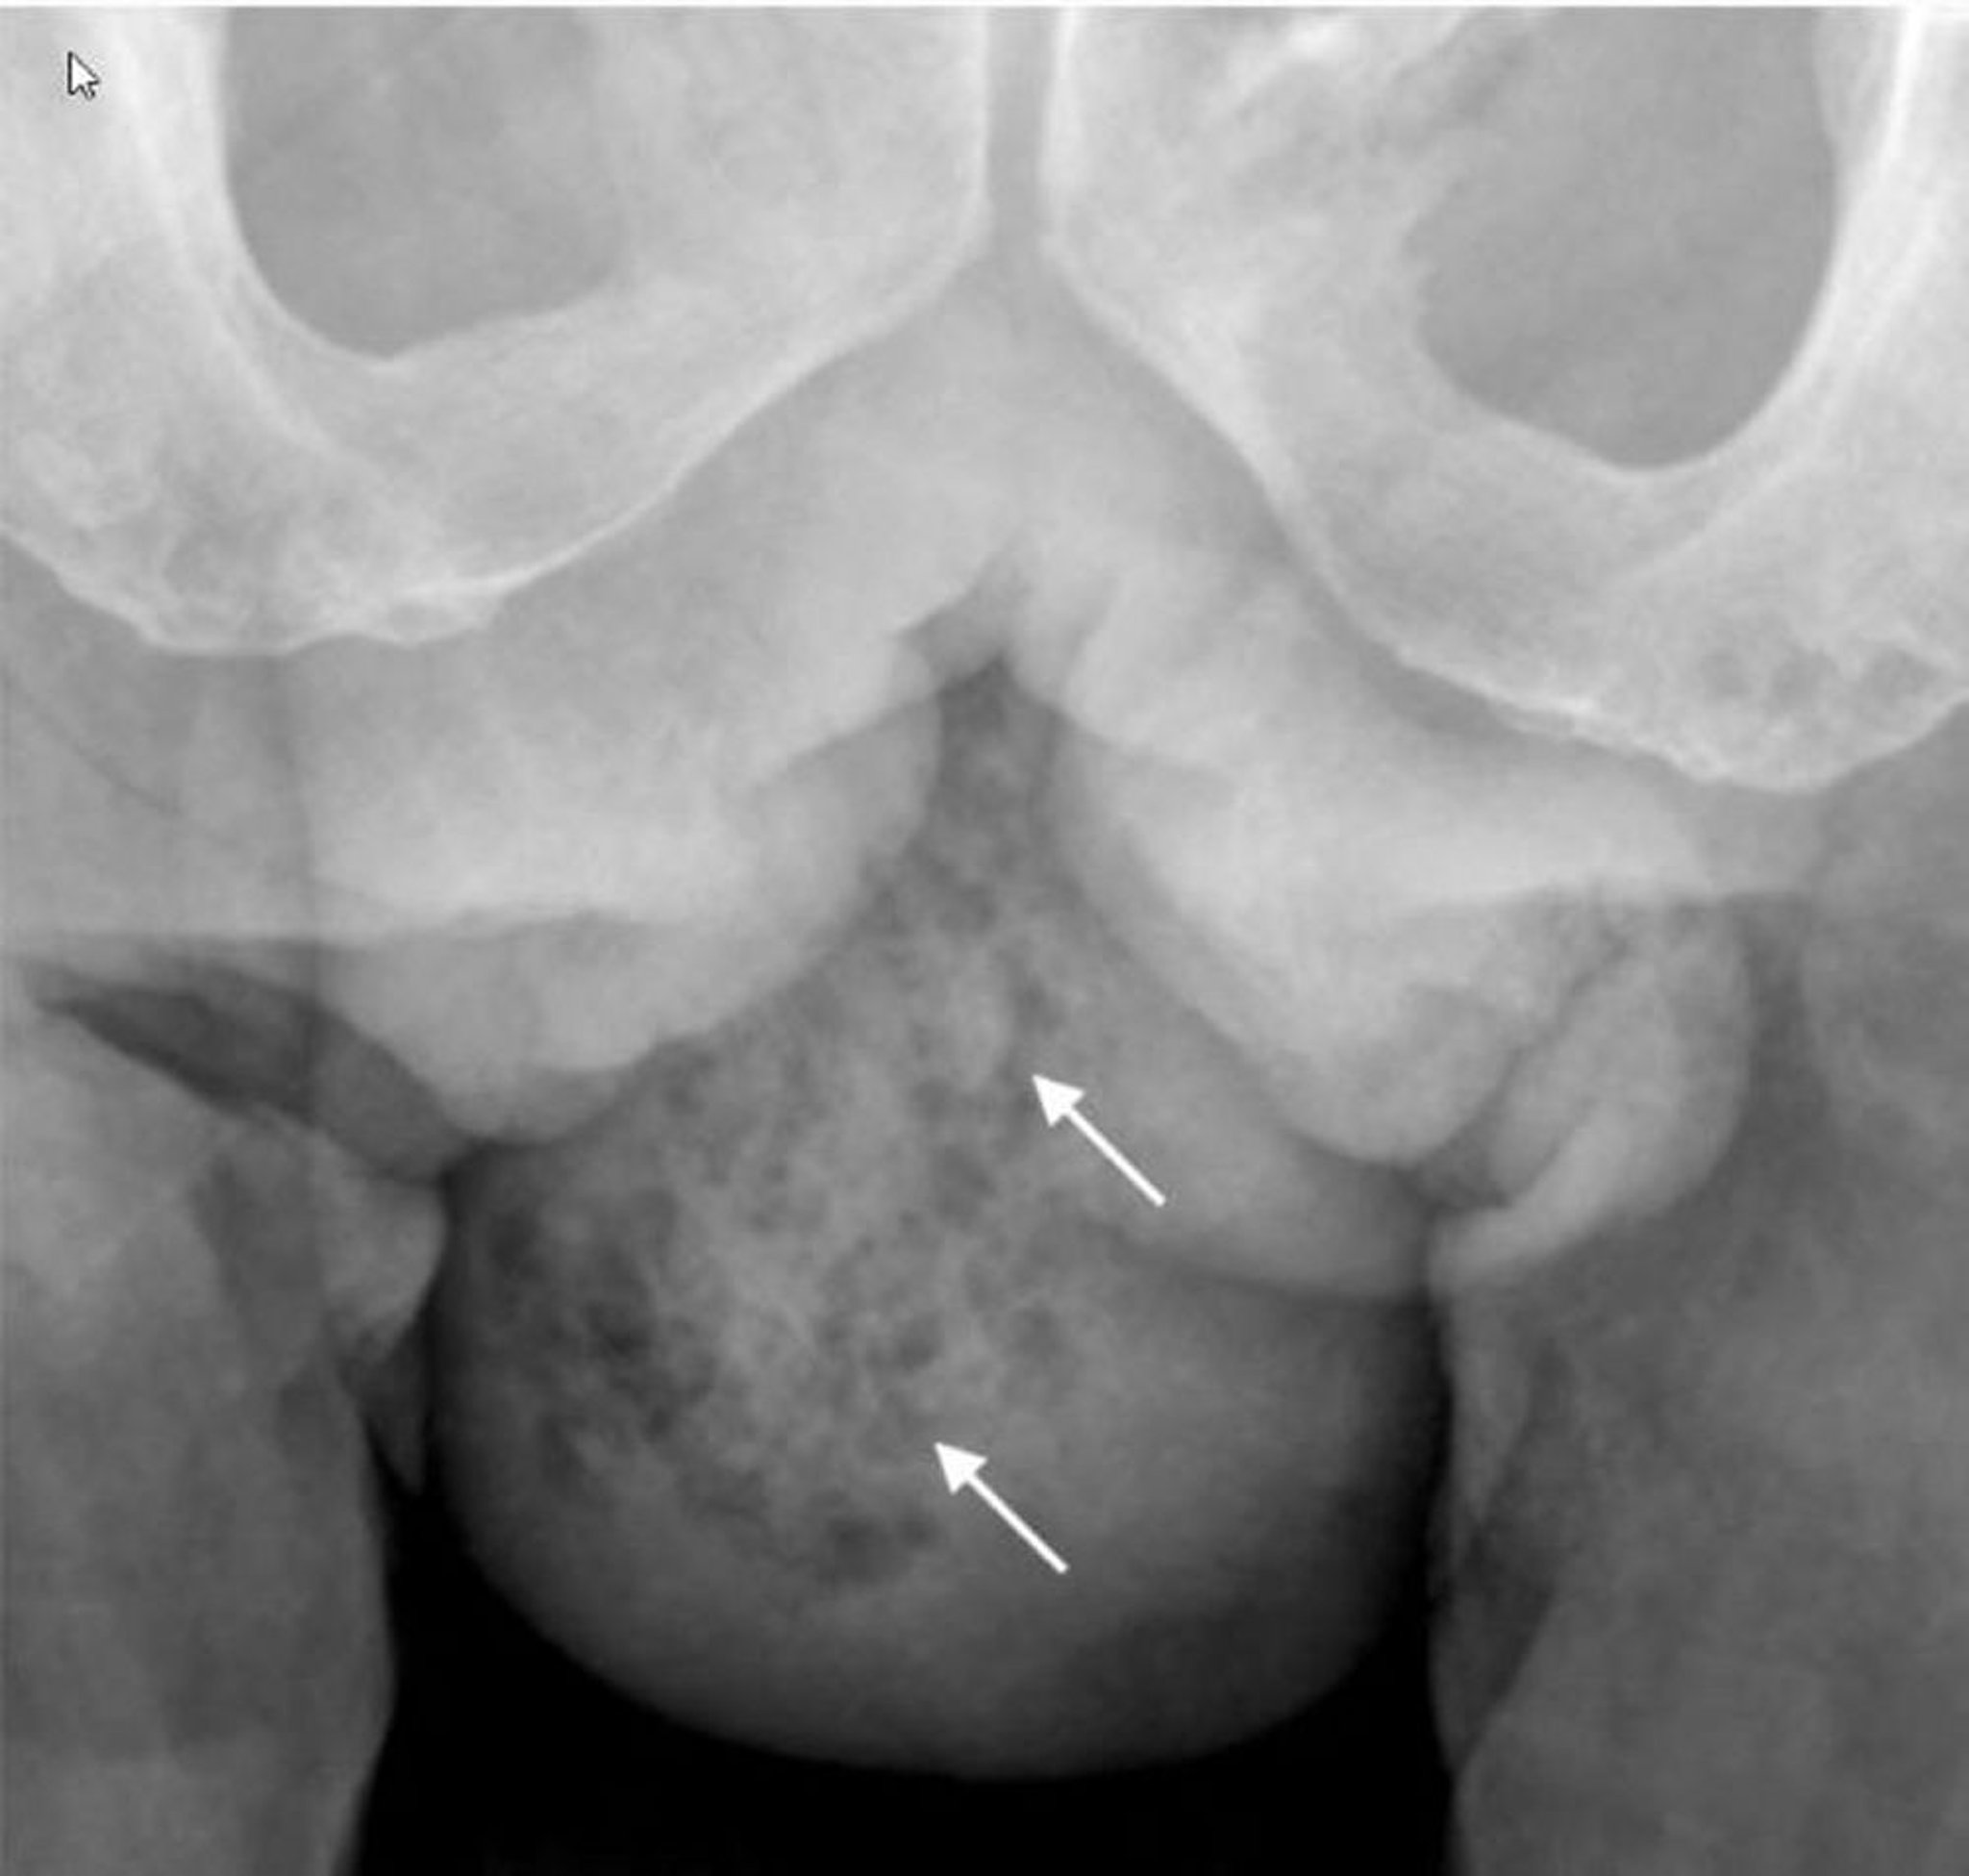

Gangrena de Fournier (radiografía)

Esta radiografía muestra gas en los tejidos blandos del hemiscroto derecho (flechas).